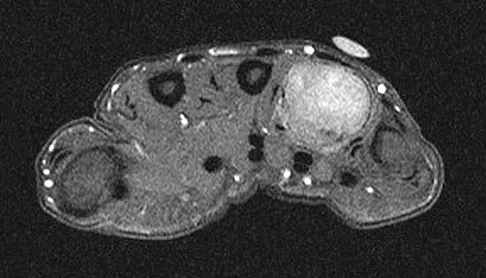

Figures 34a through 34c show an axial proton density (spin echo long TR, short TE) image, a sagittal inversion recovery (STIR) image, and a sagittal T1-weighted (short TR, short TE) image of the left thigh. What is the most likely diagnosis?

Explanation

The images reveal a region of increased signal within the rectus femoris muscle with mild, ill-defined surrounding edema. The presence of high intensity signal on the T1-weighted image favors acute blood, in this case associated with a rectus femoris muscle tear or fatty tissue. However, because of fat suppression, a fatty lesion or lipoma would be dark on STIR, rather than bright as in this image. Most foreign bodies are low intensity signal and if small, are difficult to evaluate with MRI. The lack of adjacent subcutaneous soft-tissue edema or surrounding fluid makes pyomyositis an unlikely diagnosis.